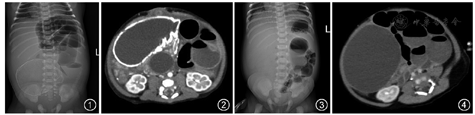

例1男,1 d,因呕吐、无便于2016年1月30日就诊。G1P1, 36周早产,出生体重3.3 kg。孕16周超声示腹腔囊性占位,羊水过多。体检:腹胀,右下腹扪及肿物。立位腹部平片示肠管扩张聚集于左腹部,右中腹见类圆形密度增高影,左半结肠管径纤细,密度较高(图1)。腹部CT检查示肠管扩张积液聚集于左腹,右中腹巨大囊性病变,囊壁钙化,乙状结肠及直肠内见高密度影填充,增强CT检查病变内部无明显强化(图2)。术中见腹腔广泛粘连,距Treitz韧带40 cm处肠管闭锁,其远段肠管坏死粘连呈团块状,可见大量钙化及粪便。

例2女,3 h,因呕吐、未排便于2016年2月14日就诊。母体孕36周超声提示肝脏下方低回声占位,G1P1,足月顺产,出生体重3.6 kg。体检:腹胀,右腹扪及较大肿物。立位腹平片示充气扩张肠管位于左腹部,右腹部致密(图3)。腹部CT检查示右腹低密度为主的边界清晰囊性占位,部分囊壁钙化,增强CT检查无强化效应,腹部肠管扩张并有气液平面(图4)。术中见右下腹巨大包裹性肿物与周围组织粘连,切开吸出大量胎便,距Treitz韧带90 cm处小肠扭转并广泛粘连。